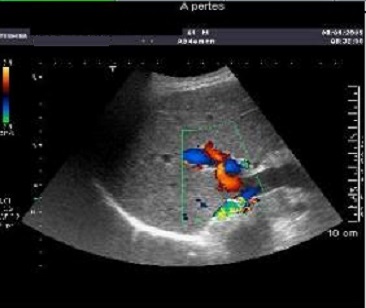

Echographie en

Doppler , methode trés utilise pour les

pathologies hepatiques , par cette methode on peut

differencie et verifie le flux monophasique et

triphasique de la veine porte et veine sús

hepatique . Par encoder de vitesse du flux sanguine

des vaiseaux intra hepatique on peut codee en

couleur le trajet des artere et veines

intrahepatique , ce qui permetre de diferencie la

richesse de vascularisation d"un tumeur ou une

lesion intrahepatique ( maligne ou begnin ) . |